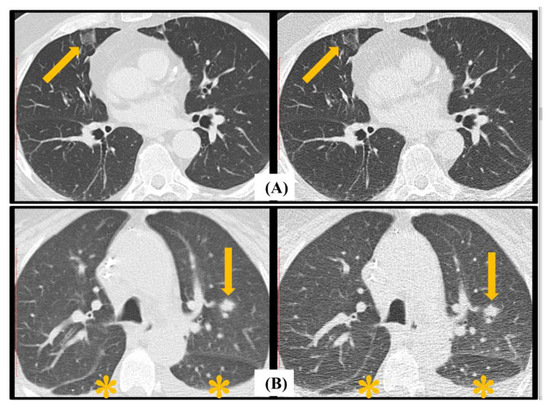

| Major: • Macro nodule. • Halo sign. • Cavitation. • Consolidation. | |

| Minor: • Ground-glass opacity (GGO). • Nodules (4–10 mm), clustered or isolated. |